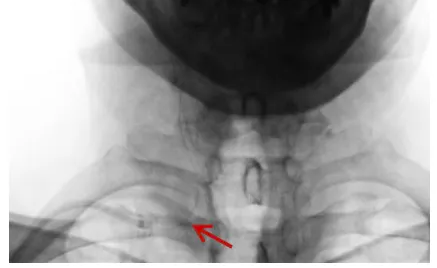

建立通道:从右侧桡动脉送入导引导管至锁骨下动脉。

测量病变:狭窄远端血管直径约 3.7 mm。